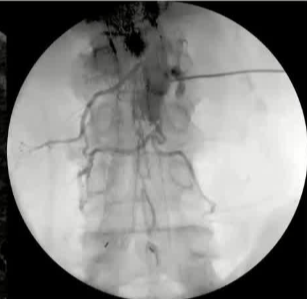

栓塞材料的可及性(例如病灶栓塞材料的可到达性)accessability (e.g. reachability of the nidus) 栓塞的预期深度intended deepness of embolization 如果需要让栓塞填满最后1mm 预期效果(例如:门静脉栓塞的炎症)intended effect (e.g. inflammation in PVE) 凝血状态(达到止血效果所需的时间)coagulation state (duration until hemostasis) 并发症(过敏、心律不齐、肺动脉高压、肝纤维化等)comorbidities (allergies, arrythmia, pulmonary hypertension, lung fibrosis etc.) 处于危险中的结构(包括下游部分-downstream和反流部分) structures at risk (downstream & backwash) 靶病变定位(浅层与深层) target lesion localization (superficial vs. deep) 不会选择一些会引起炎症的东西,因为那会病人来说真的很痛苦浅层病变 栓塞所需的速度(例如:危及生命的出血情况)required speed of embolization (e.g. life threatening hemorraghe) 院外专业人员(DSA技术人员和介入放射科医生)local expertise (technicians & IR's) 可用性与定价 availabilty & pricing Patient assessment for the choice of the ideal liquid emboli 影像学 62岁 男性

腹腔侧支循环